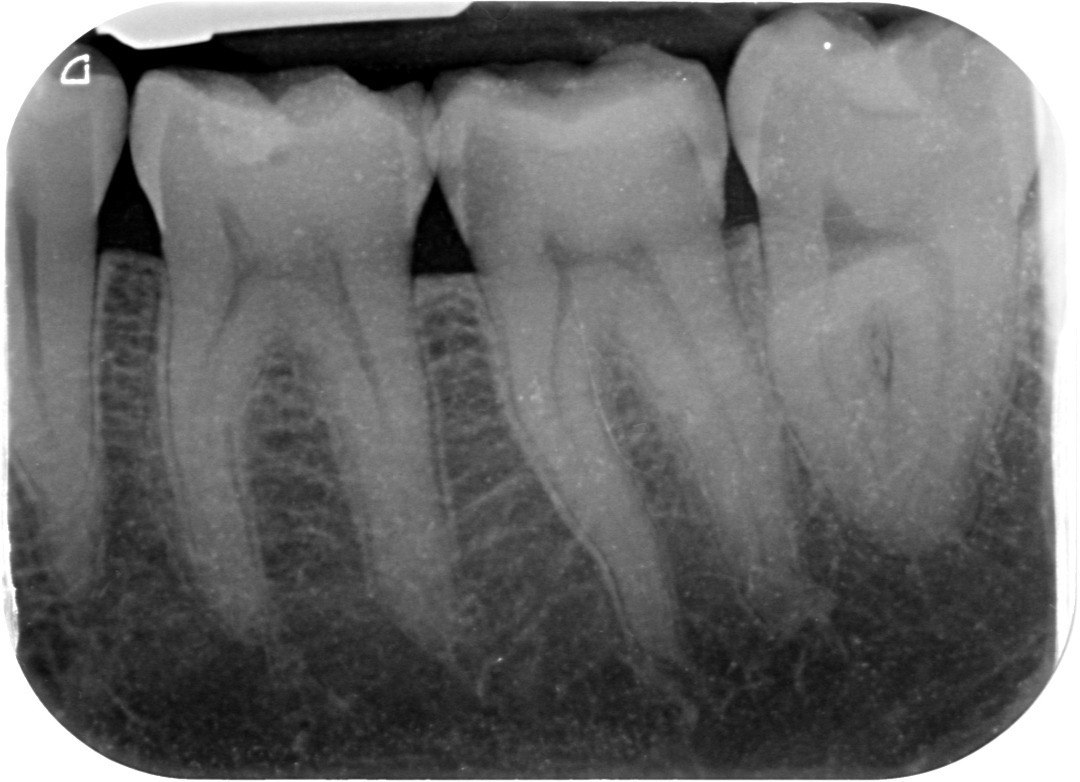

9. Which surfaces shows root caries?

10: What is the caries level on occlusal of the tooth # 2.7?

11. What is the caries level of the distal surface of the toot # 3.5?

12. Which surface shows Cervical burn out?

13. what are the radiolucency features in mesial and distal root surface of the tooth # 4.5 respectively?